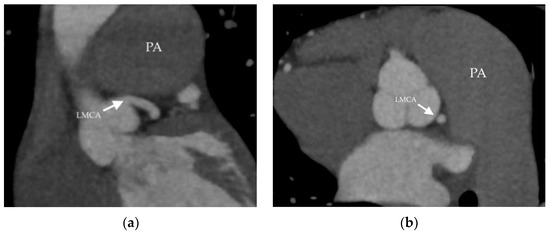

- Akbal, O.Y.; Kaymaz, C.; Tanboga, I.H.; Hakgor, A.; Yilmaz, F.; Turkday, S.; Dogan, C.; Tanyeri, S.; Demir, D.; Bayram, Z.; et al. Extrinsic Compression of Left Main Coronary Artery by Aneurysmal Pulmonary Artery in Severe Pulmonary Hypertension: Its Correlates, Clinical Impact, and Management Strategies. Eur. Heart J. Cardiovasc. Imaging 2018, 19, 1302–1308. [Google Scholar] [CrossRef]

- Hernández, V.; Ruiz-Cano, M.J.; Escribano, P.; Sánchez, M.A. Complications of Proximal Pulmonary Artery Aneurysm in Patients with Severe Pulmonary Arterial Hypertension. Rev. Esp. Cardiol. 2010, 63, 617–618. [Google Scholar] [CrossRef]

- Caldera, A.E.; Cruz-Gonzalez, I.; Bezerra, H.G.; Cury, R.C.; Palacios, I.F.; Cockrill, B.A.; Inglessis-Azuaje, I. Endovascular Therapy for Left Main Compression Syndrome. Case Report and Literature Review. Chest 2009, 135, 1648–1650. [Google Scholar] [CrossRef]

- Galiè, N.; Saia, F.; Palazzini, M.; Manes, A.; Russo, V.; Bacchi Reggiani, M.L.; Dall’Ara, G.; Monti, E.; Dardi, F.; Albini, A.; et al. Left Main Coronary Artery Compression in Patients With Pulmonary Arterial Hypertension and Angina. J. Am. Coll. Cardiol. 2017, 69, 2808–2817. [Google Scholar] [CrossRef]

| PA diameter (mm) | 52 | 56 | 58 | 66 |

| PA diameter (mm) | 42 | 45 | 52 | 53 |